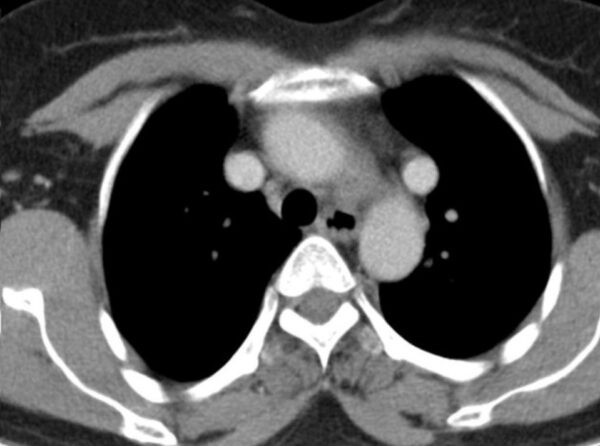

Case 7

https://radiopaedia.org/cases/double-superior-vena-cava-3

CT

CVS